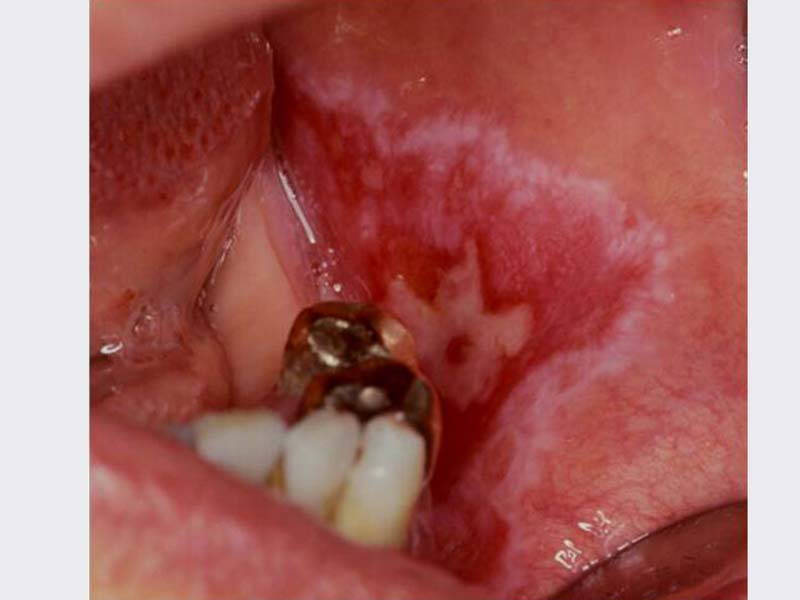

口腔黏膜病變治療

• 口腔黏膜病變治療